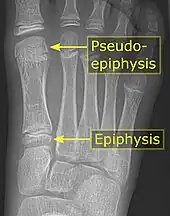

Pseudo-epiphysis

A pseudo-epiphysis is an epiphysis-looking end of a bone where an epiphysis is not normally located.[11] A pseudo-epiphysis is delineated by a transverse notch, looking similar to a growth plate.[11] However, these transverse notches lack the typical cell columns found in normal growth plates, and do not contribute significantly to longitudinal bone growth.[12] Pseudo-epiphyses are found at the distal end of the first metacarpal bone in 80% of the normal population, and at the proximal end of the second metacarpal in 60%.[11]